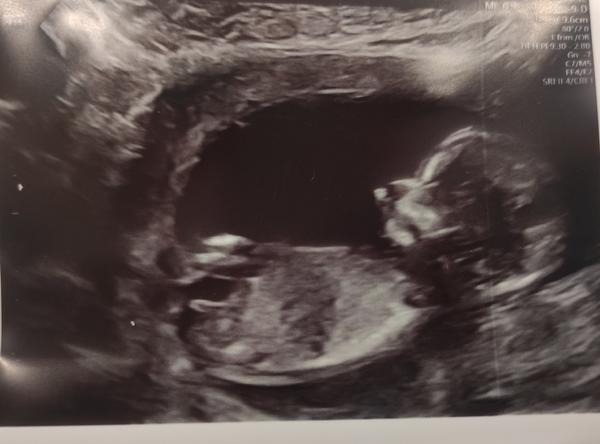

Na screeningu v 14. tt mi vyšetřující lékařka řekla, že to vidí na chlapečka, ale já tedy, ať koukám, jak koukám, tak mi podle sklonu pohlavního hrbolku (pokud to, co vidím, je opravdu pohl. hrbolek) tedy vychází téměř ukázková holčička, a proto by mne zajímal i Váš názor.

posuzovat pohlaví z jednoho snímku a v prvním trimestru má své velké limitace a vždy je to jen hrubý odhad a dojem, ale máte pravdu, vypadá to spíše na holčičku. Stejně si počkejte na ultrazvuk ve 20. týdnu, tam to bývá již jednoznačné.